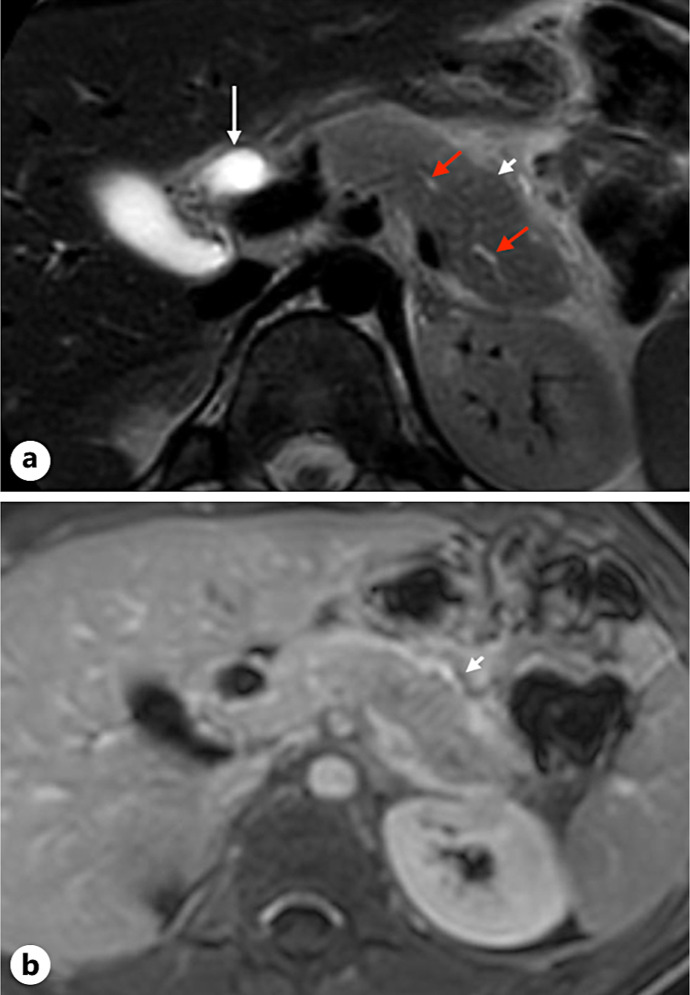

Case presentation: A 14-year-old adolescent presented to the emergency department with abdominal pain, vomiting, and jaundice. A combination of biological and radiological assessments led to the diagnosis of AIP. The patient experienced a swift and complete recovery without intensive treatment.